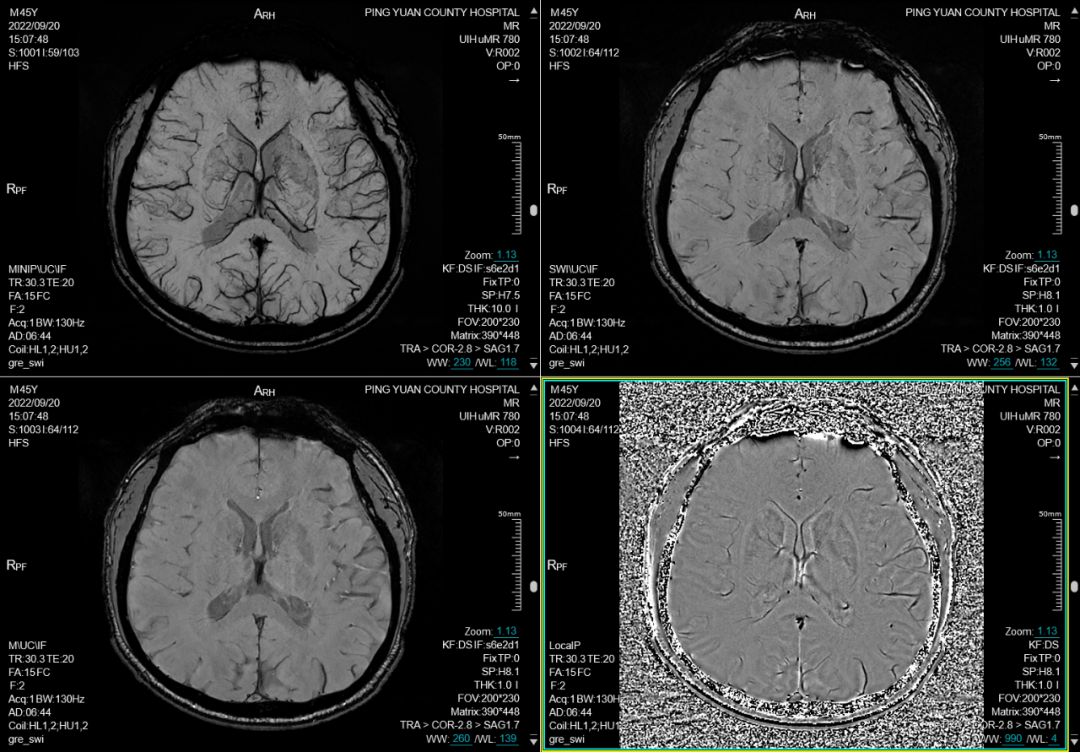

三、磁敏感加权成像技术(SWI): 磁共振磁敏感加权成像(SWI)比常规磁共振检查技术更敏感地显示出血,甚至是微小出血。对脑小血管病、血管炎、海绵状血管瘤、静脉畸形、淀粉样脑血管病(CAA)、CAA相关血管炎、外伤后轴索损伤、蛛网膜下腔出血、脑铁沉积的神经变性病(NBIA)等疾病有重要诊断价值。

联影磁共振怎么样平原县第一人民医院联影uMR780 光梭3.0T磁共振正式投入使用,开启医学影像新时代!_https://www.jmylbn.com_新闻资讯_第8张